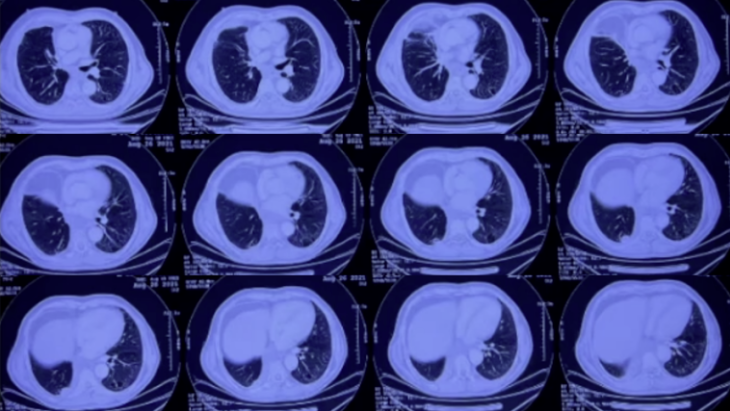

5. 影像学

2021年5月19日(外院手术治疗前),患者胸部CT示:右下肺占位性病变(图1)。术后病理分期提示为腺鳞癌。

图1 患者外院胸部CT(2021-05-19)

2021年8月26日复查胸部CT提示复发,右下肺病灶较5月进一步增大(图2)。10月12日再次复查胸部CT,右下肺病灶仍清晰可见(图3)。

图2 患者外院胸部CT(2021-08-26)

图3 患者外院胸部CT(2021-10-12)